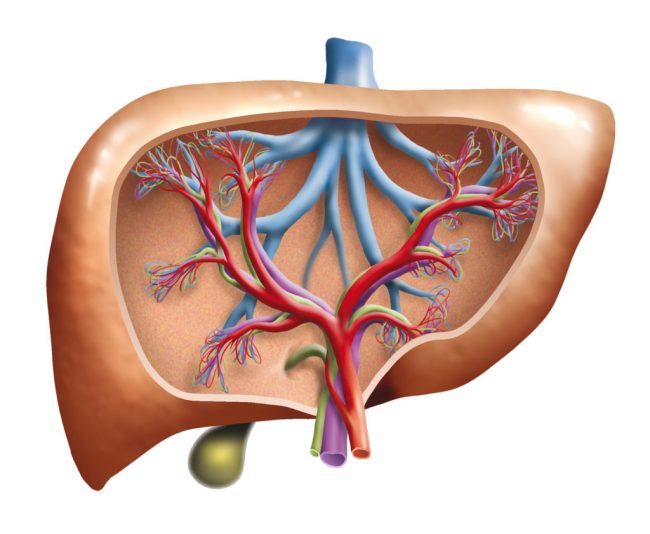

Unter einer Entgiftung versteht man die Ausscheidung unerwünschter Stoffe aus dem Organismus. An der Entgiftung und Ausscheidung sind hauptsächlich die Organe Leber, Nieren, Darm, Haut, Lymphsystem und die Lunge beteiligt. Die Entgiftung kann mit Hilfe von Zeolith unterstützt und beschleunigt werden. Entgiftung: Was versteht man darunter? Die Entgiftung ist der natürliche Prozess des Körpers,…